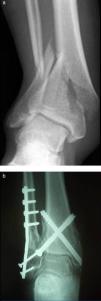

In G2, the fractures were synthesized using two cannulated AO screws inserted percutaneously (Fig. 1). The screws were placed in a cross or X shape, from distal to proximal (from medial-posterior to lateral-anterior and from lateral-posterior to medial-anterior). A fluoroscope was used to assess the correct placement of the screws.

There were 11 fibular fractures in G1 and 8 in G2. The fibula was stabilized in the case of displaced or distal third shortened fractures, and in cases of fractures located between 40 and 50mm from the ankle joint (G1: 9; G2: 8). In all cases, the synthesis of the fibula was carried out ahead of the tibial fracture. Five patients in G1 underwent sequential treatment, including application of an external fixator in the emergency room, and were subsequently intervened for the definitive synthesis after a mean period of 9.8 days (range: 6–14 days) (Fig. 2).